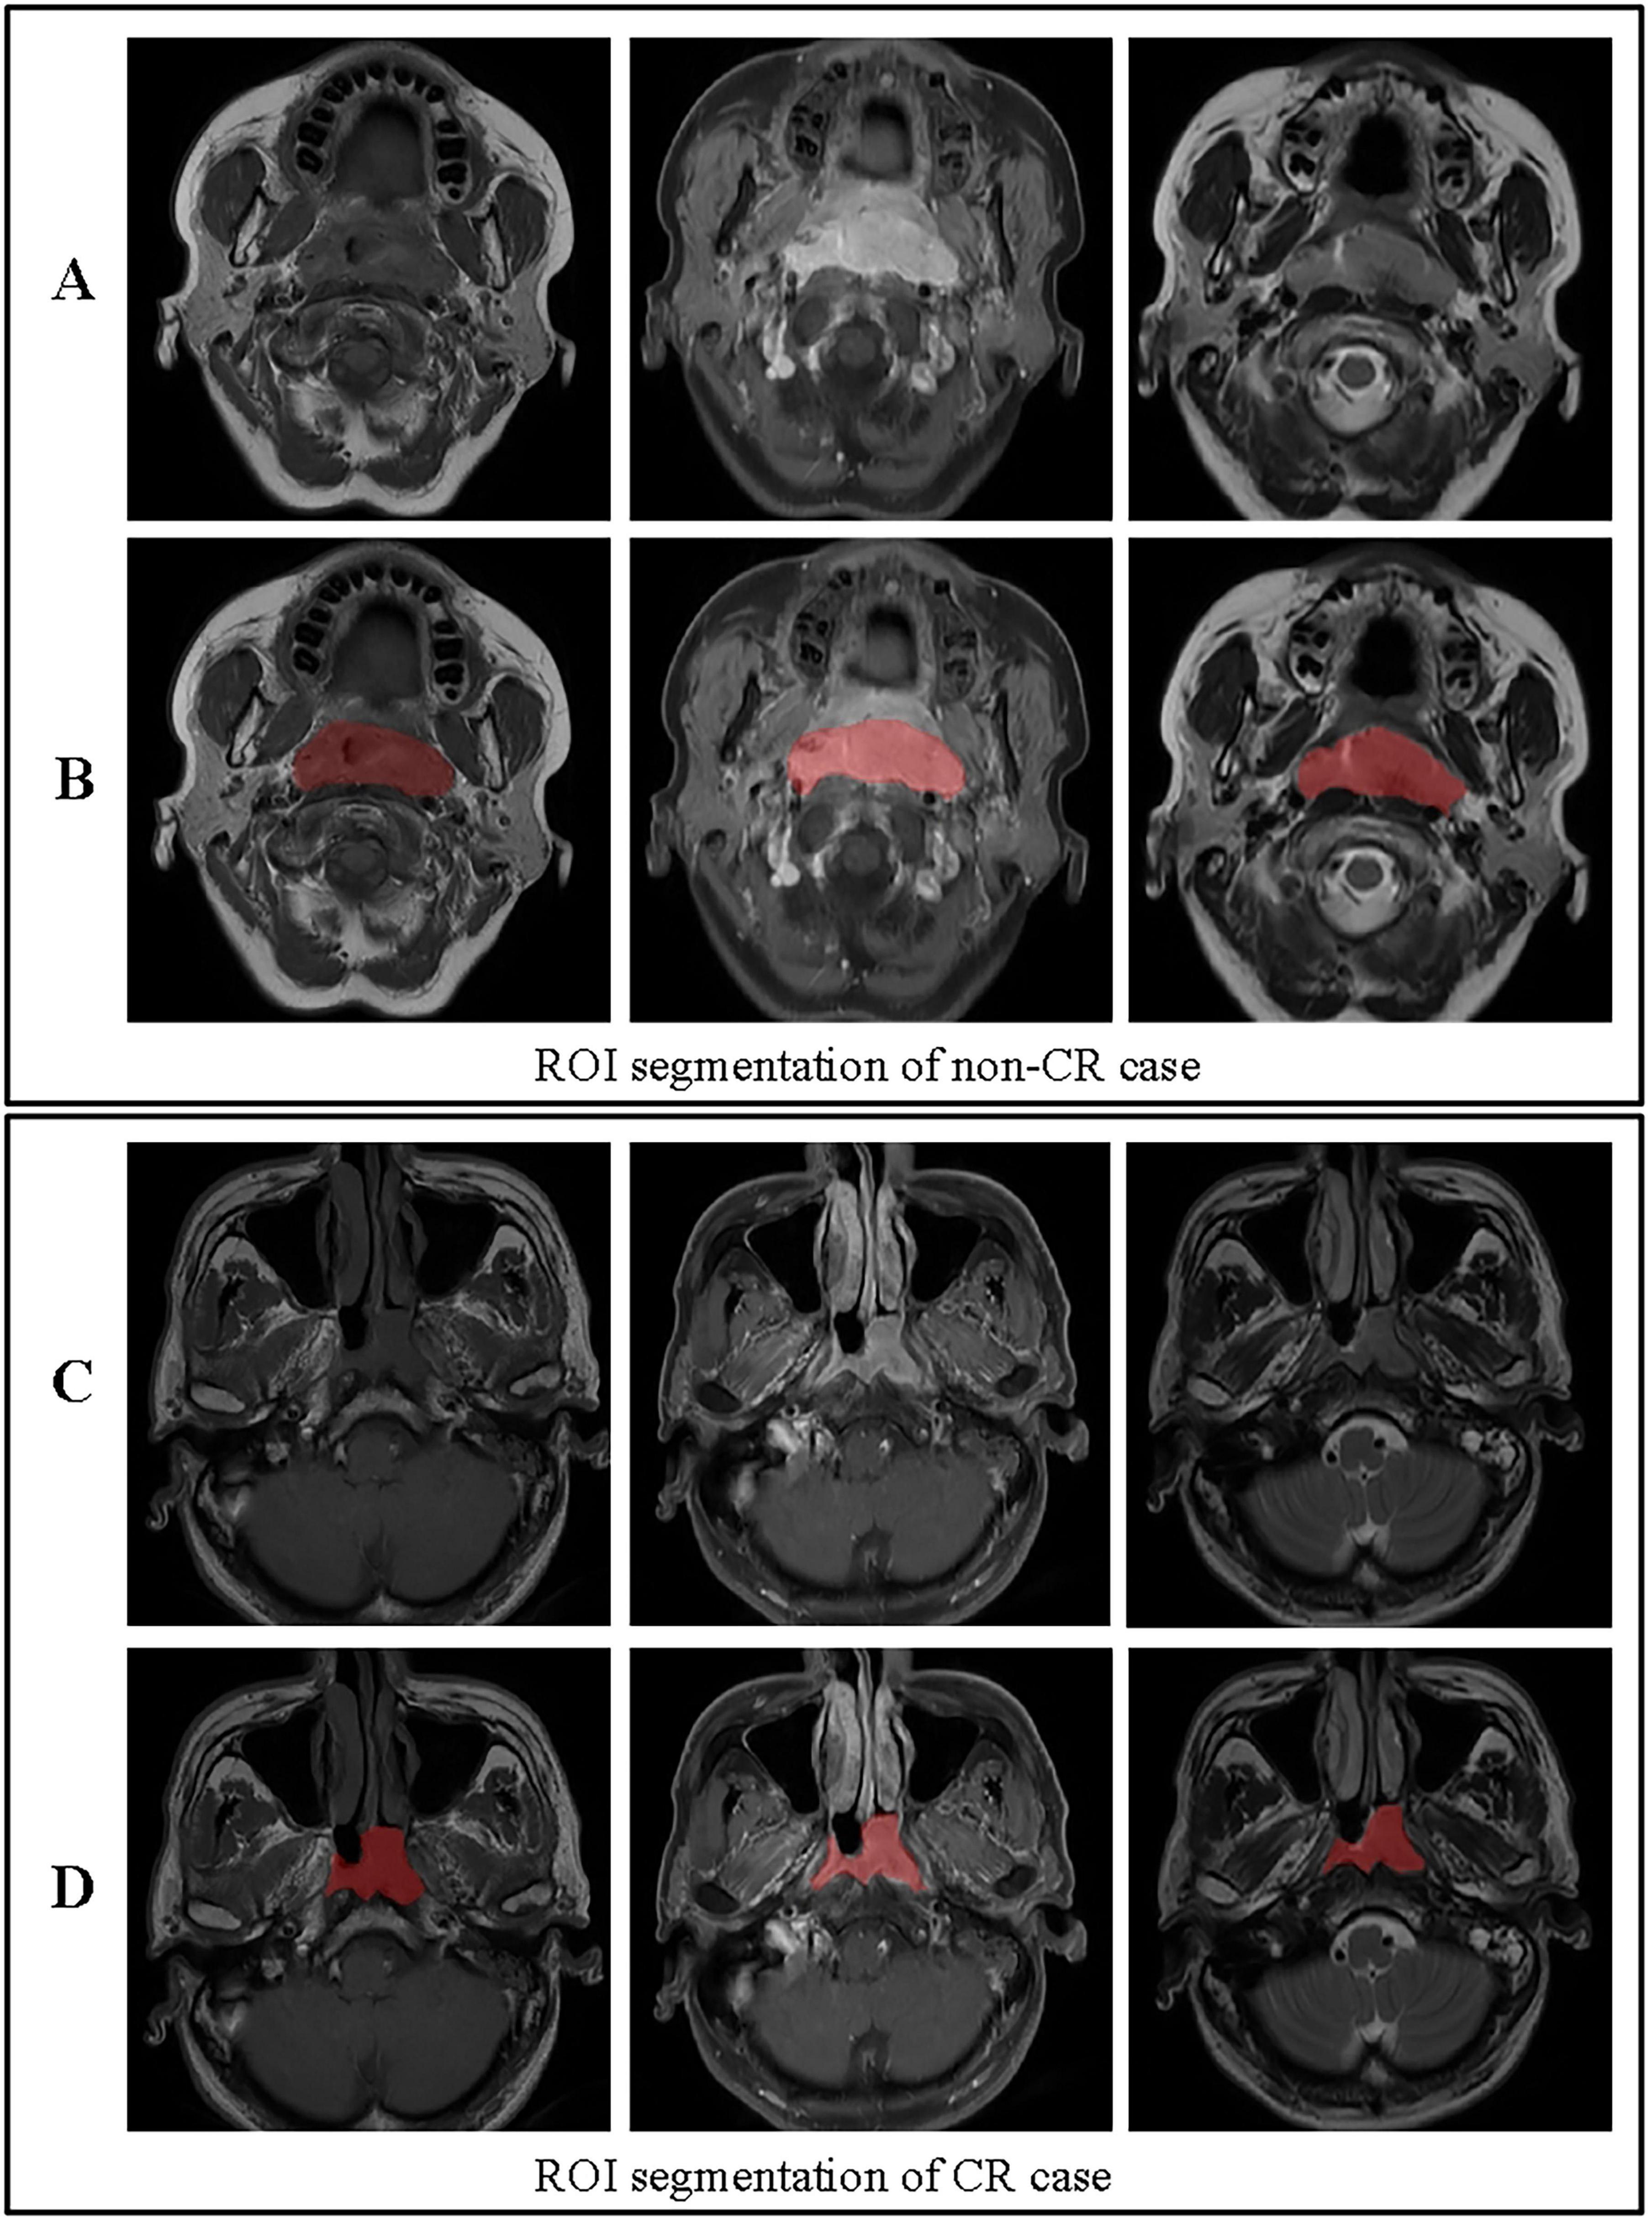

Volumes of interest (VOIs) were manually delineated on the primary nasopharyngeal tumor on all sequences (T1WI, T2WI, and CE-T1WI) by two radiologists (R1 and R2, with 10 and 15 years of experience in head and neck imaging, respectively) using ITK-SNAP software. Both readers were blinded to the clinical outcomes and followed a pre-defined segmentation protocol that specified the inclusion of the entire gross tumor volume while excluding obvious necrotic regions, vessels, and adjacent normal tissue as shown in Figure 3 (27). To assess inter-observer variability, both radiologists independently segmented a randomly selected subset of 30 patients. The intraclass correlation coefficient (ICC) was calculated for each feature extracted from these duplicate segmentations. Features with an ICC > 0.85 were considered robust and retained for further analysis. The remaining cases were segmented by R1 and reviewed by R2; any discrepancies were adjudicated by a senior radiologist (20 years of experience) to establish a consensus segmentation gold standard (28).

FIGURE 3

ROI segmentation for non-CR and CR cases. (A) Original images for a non-CR case, from left to right: T1, contrast-enhanced T1-weighted, and T2 sequences. (B) ROI segmentation for the non-CR case on T1, contrast-enhanced T1-weighted, and T2 images. (C) Original images for a CR case, from left to right: T1, contrast-enhanced T1-weighted, and T2 sequences. (D) ROI segmentation for the CR case on T1, contrast-enhanced T1-weighted, and T2 images. This figure demonstrates the differences in ROI segmentation between non-CR and CR cases, highlighting the segmented tumor regions in red.